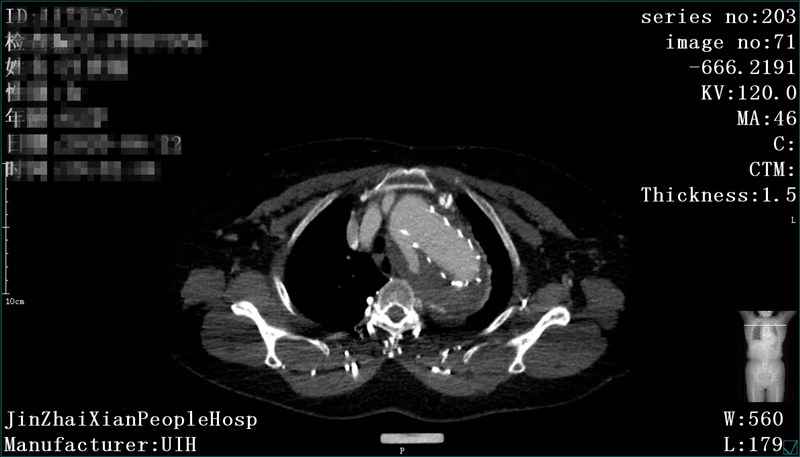

患者朱某,女,72岁,家住我县全军乡,6月22日下午突发胸背部剧痛至我院急诊科就诊,行胸部CTA检查考虑主动脉夹层(Debakey  III型),急请我科会诊。会诊后以主动脉夹层收住介入科,积极给予稳定血压、镇痛治疗。因该患者为先天性失聪失语,沟通十分困难、不畅,祝国臣副主任通过患者女儿耐心与患者沟通,详细询问病情,仔细检查患者体征,并与患者家属说明患者的病情与风险,患者家属了解病情后,十分感激祝国臣医生,决定手术治疗。我科积极完善相关术前准备及手术所需材料,于 7月5日在DSA下行“主动脉、左锁骨下动脉造影+分支型覆膜支架腔内隔绝术”,术中患者破口及真假腔显示明确,破口位置与左锁骨下动脉距离较近,给手术带来一定的困难,根据患者术中造影情况,制定详细手术方案,既保证覆膜支架安全成功释放,又保证不影响左锁骨下动脉血供。术后患者病情平稳,现患者血压、心率稳定,患者胸背部疼痛症状消失。

术前CT显示主动脉夹层真假腔及破口位置